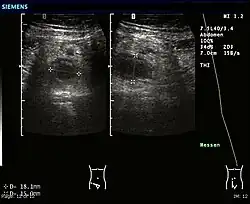

Échographie : appendicite.

L'imagerie n'est utilisée qu'en cas de doute sur le diagnostic :

• l’échographie apporte des arguments de diagnostic différentiel, et aide au diagnostic d’abcès appendiculaire ;